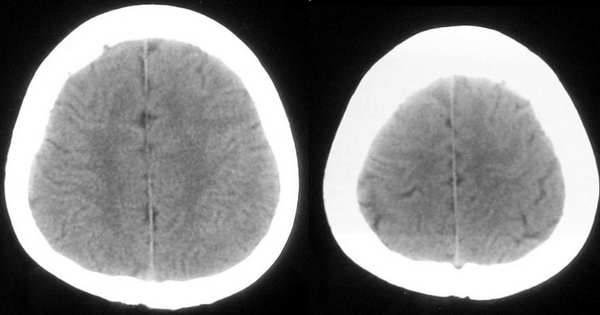

患者,女,32岁,时有头晕,无恶心呕吐。

这个病例为正常的头部ct表现,只是由于摆位不正而造成了诸多疑问,所以在工作中要注意摆位问题。

我认为是正常的颅脑影像。左侧颞顶叶脑组织示略高密度结构是近外侧裂区的正常皮质结构,不是灰质移位。由于摆的位置不正,左侧的脑组织较右侧的低一个层面。